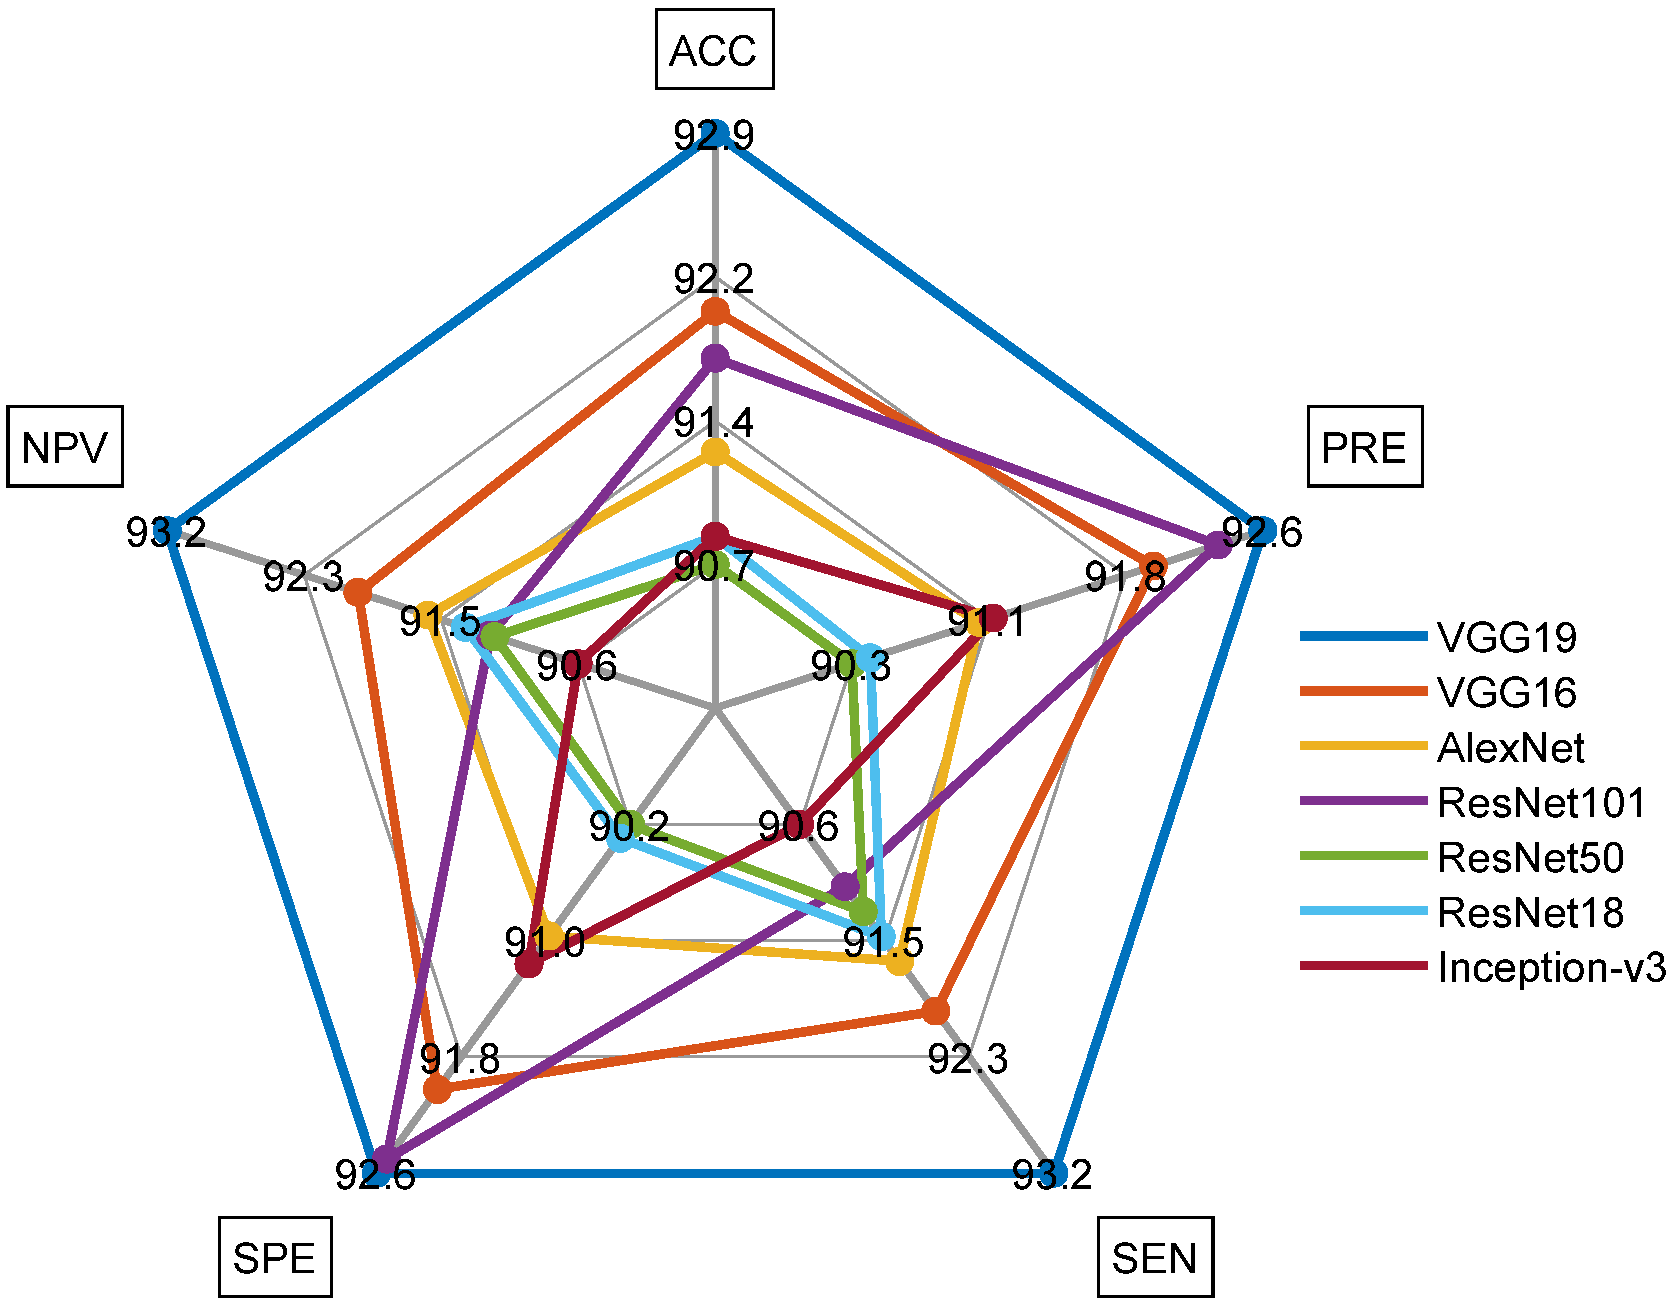

| Scheme | TP | FN | TN | FP | ACC% | PRE% | SEN% | SPE% | NPV% |

|---|---|---|---|---|---|---|---|---|---|

| VGG19 | 979 | 71 | 972 | 78 | 92.9048 | 92.6206 | 93.2381 | 92.5714 | 93.1927 |

| VGG16 | 966 | 84 | 966 | 84 | 92.0000 | 92.0000 | 92.0000 | 92.0000 | 92.0000 |

| AlexNet | 962 | 88 | 955 | 95 | 91.2857 | 91.0123 | 91.6190 | 90.9524 | 91.5628 |

| ResNet101 | 956 | 94 | 971 | 79 | 91.7619 | 92.3671 | 91.0476 | 92.4762 | 91.1737 |

| ResNet50 | 958 | 92 | 947 | 103 | 90.7143 | 90.2922 | 91.2381 | 90.1905 | 91.1453 |

| ResNet18 | 960 | 90 | 948 | 102 | 90.8571 | 90.3955 | 91.4286 | 90.2857 | 91.3295 |

| Inception-v3 | 951 | 99 | 957 | 93 | 90.8571 | 91.0920 | 90.5714 | 91.1429 | 90.6250 |